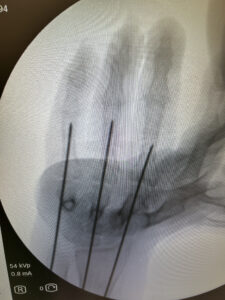

A técnica abaixo, utilizada em fraturas muito proximais de falange proximal na qual o fio de Kirschner é passado através da cabeça do metacarpo é conhecida como técnica de:

Qual é essa técnica?